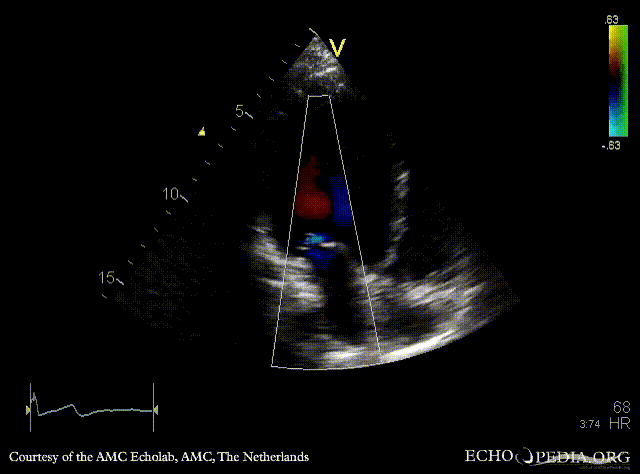

Dilated cardiomyopathy

A2CH A3CH: Color Doppler, moderate mitral regurgitation

A4CH: Color Doppler, moderate mitral regurgitation